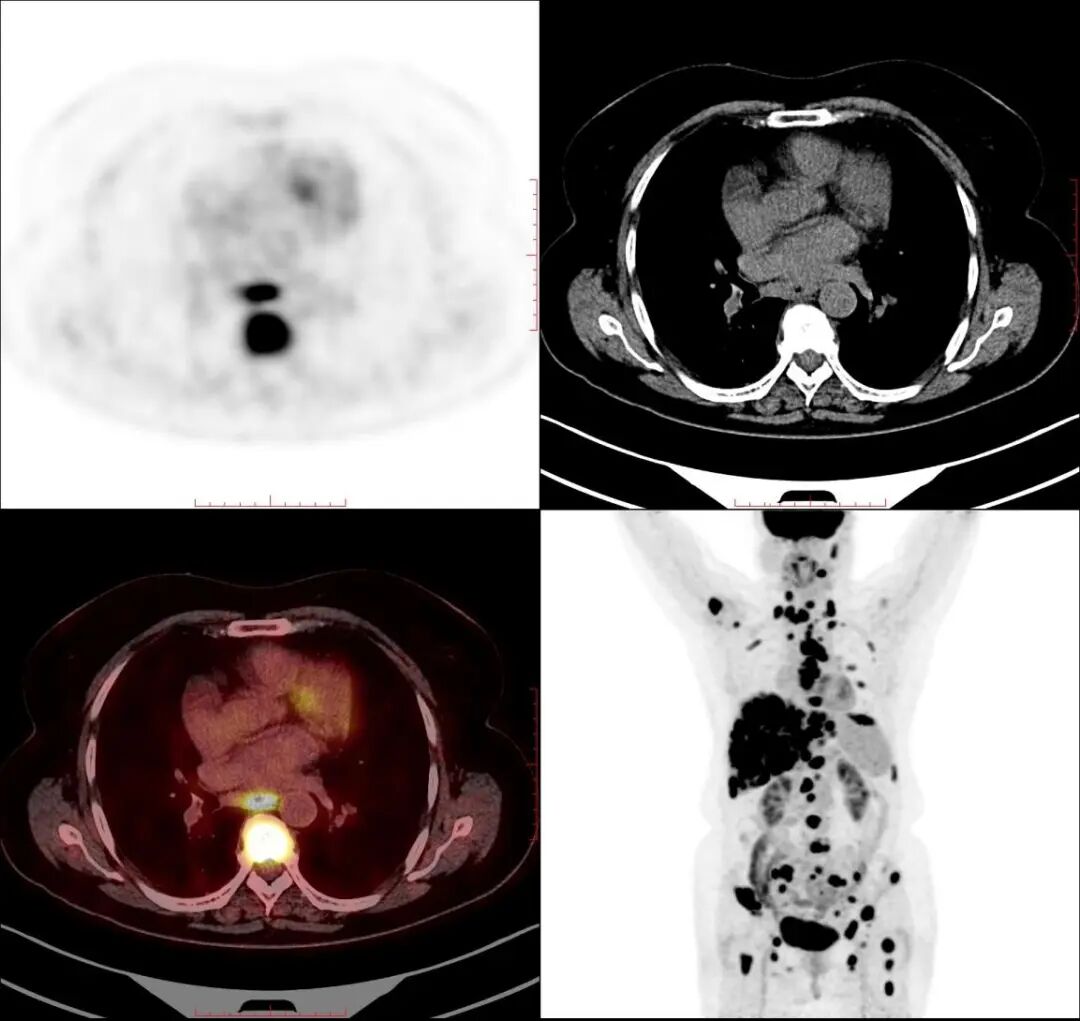

右肺癌伴多发全身转移

图片